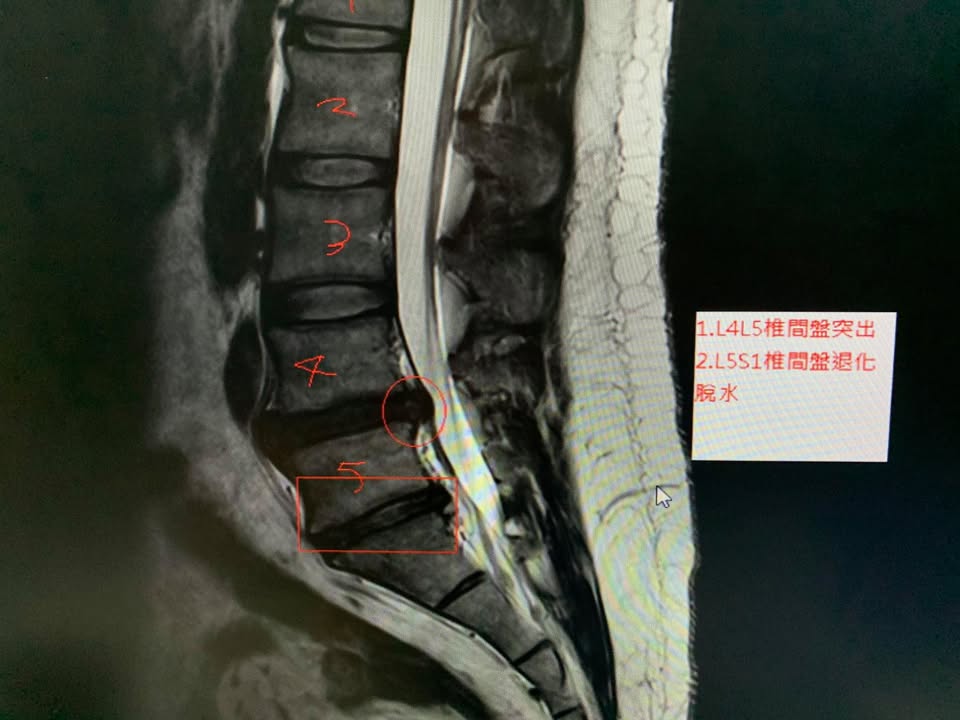

鄭先生抱怨右側大腿很痛,屁股也會痛,很酸痛,走路快沒辦法走下去,疼痛大約快一年,最後才去醫院拍攝MRI證實椎間盤突出症,L4L5突出,這中間已經做過物理治療拉了快三十次,效果不如預期,骨科醫師建議開刀,因為畏懼開刀,所以來接受脊椎整合中醫微創療法

✅診斷:椎間盤突出壓迫神經根

多裂肌萎縮